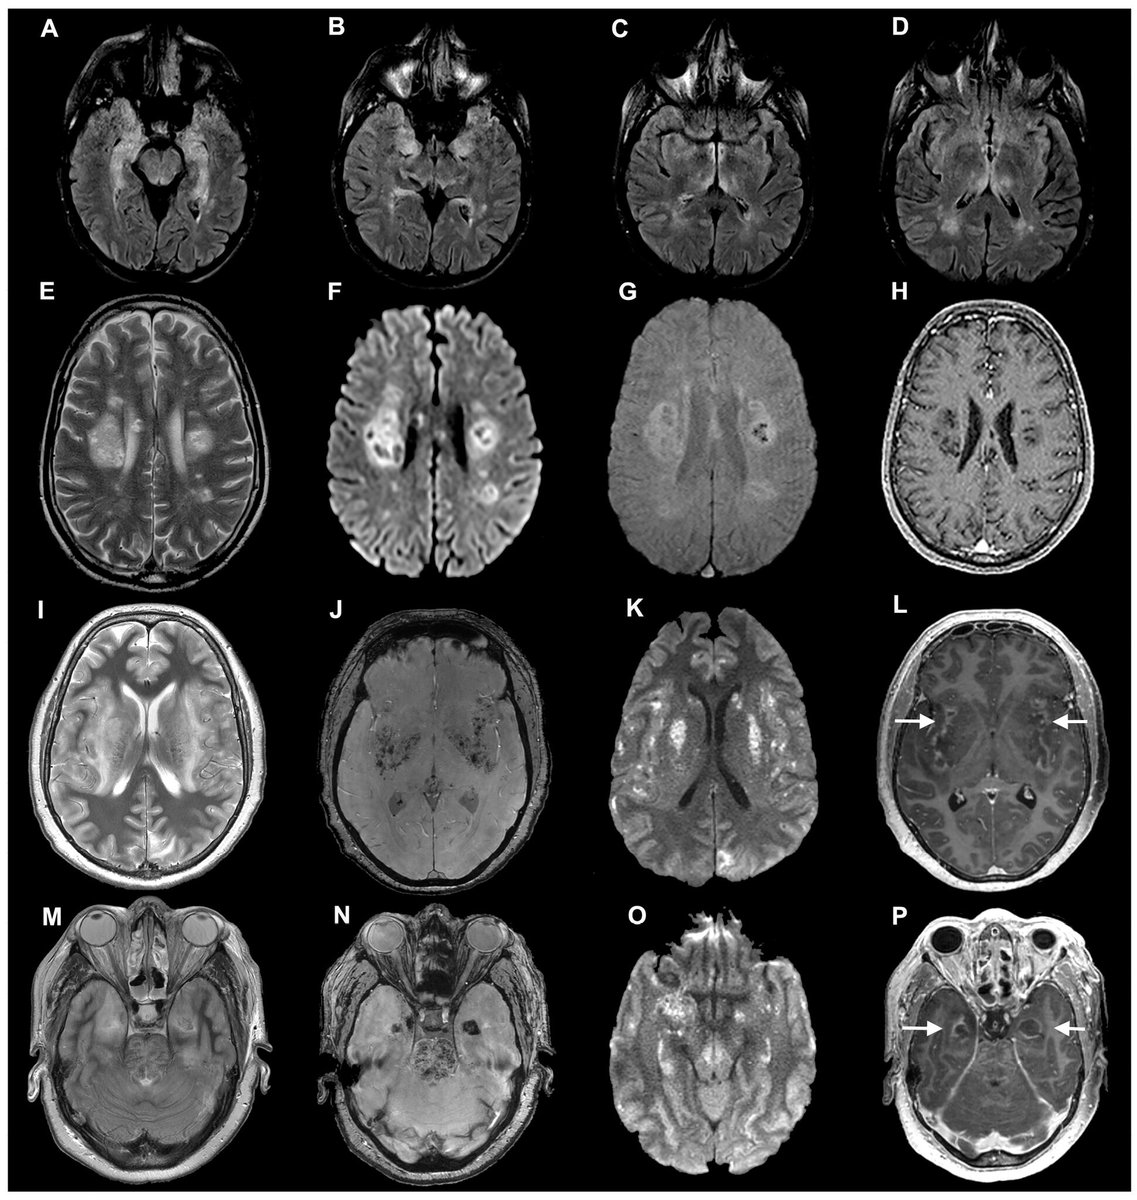

Es sabido que el #SARSCoV2 afecta a un gran número de tejidos y órganos, entre ellos el cerebro. Un porcentaje de los enfermos #COVID19 sufren síntomas neurológicos: dolores de cabeza, confusión, delirios, lo que sugiere que el virus pudiera penetrar/atacar el cerebro.

Hay un preprint (no revisado por pares) interesante que estudia la posible entrada del coronavirus a nivel del tejido cerebral y lo hace empleando diferentes modelos experimentales y estrategias. Las explico una a una. biorxiv.org/content/10.110…

El tercero es a través de una biopsia a una paciente fallecido con #COVID19, y en la que pudo detectarse el coronavirus en neuronas corticales. Todo ello sugeriría, la capacidad de invasión cerebral del virus y explicaría algunos de sus efectos neurológicos. Image